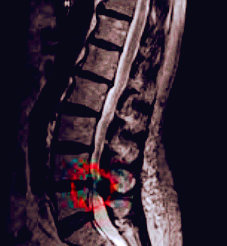

척추협착증 진단

척추협착증 진단, CT와 MRI 촬영 등을 통해서 척추관 크기와 주변 관절과 인대, 추간판의 상태를 알아보고 종합적으로 진단을 하게 됩니다. 근전도 검사와 신경전도 검사도 함께 병행해서 하게 되겠습니다.